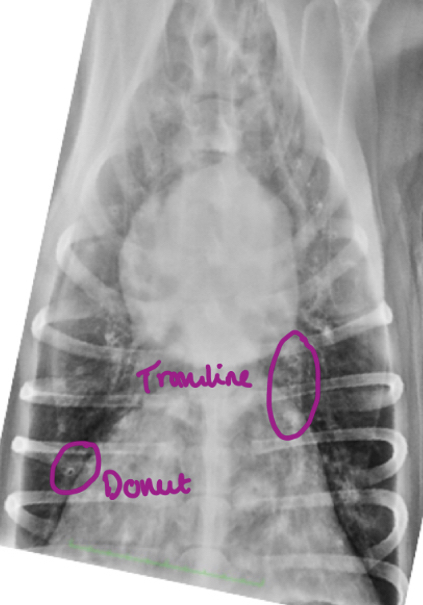

We can see tramlines and donuts. Which lung pattern is shown here?

A

Interstitial

This is like looking through mist or a lace curtain; structures are not obliterated, but are greyed-out.

Donuts and tramlines = abnormal thickening of the airway (bronchiole) walls -> bronchial pattern